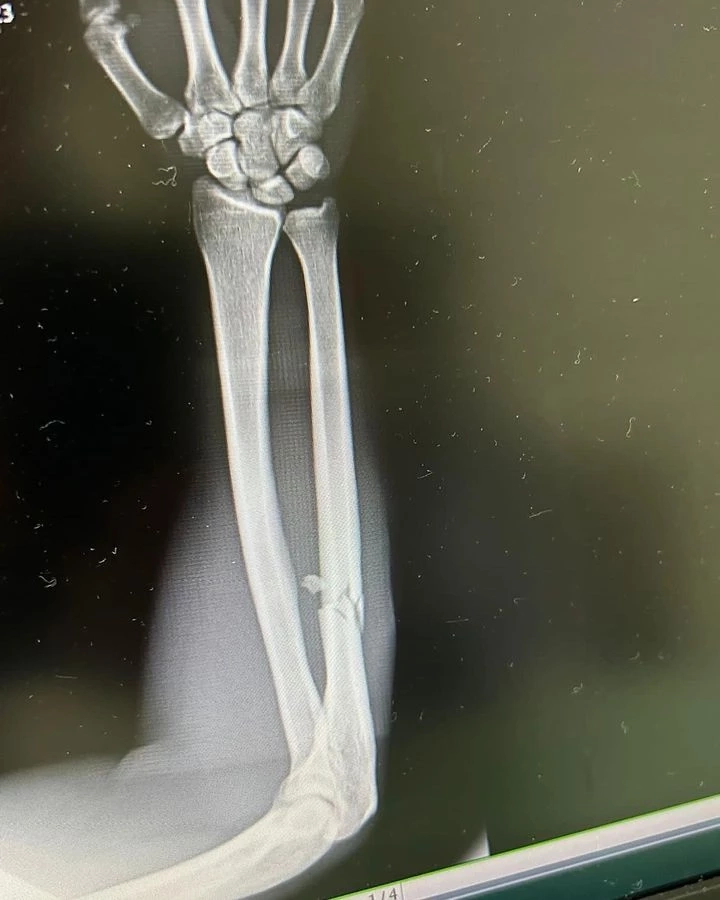

เผยภาพเอ็กซ์เรย์อาการล่าสุดของ ดาวิต คิเรีย หลังโดน ตะวันฉาย พีเค.แสนชัยฯ เตะจนกรรมการสั่งยุติการชก ในศึก ONE Fight Night 13

เปิดฉากมา “ตะวันฉาย” ทักทายด้วยการสาดแข้งซ้ายอาวุธถนัด ด้าน “ดาวิต” โชว์สเต็ปฟุตเวิร์กพร้อมออกหมัดเข้ากดดันนักชกไทย เข้ายกสอง “ดาวิต” ยังใช้ความเก๋าเดินเข้าหาต่อเนื่อง แต่ก็ถูก “ตะวันฉาย” ดักเตะซ้ายอย่างหนักหน่วง เริ่มยกสามไม่ทันไร “ตะวันฉาย” แจกแข้งซ้ายฟาดแขน “ดาวิต” สุดแรงเกิดเล่นเอาแขนห้อย จนกรรมการต้องยุติการแข่งขันเพื่อความปลอดภัยของนักกีฬา

ส่งให้กรรมการชูมือ “ตะวันฉาย” ชนะทีเคโอไปในนาทีที่ 0:29 ของยกสาม พร้อมหยิบสดโบนัสจากบิ๊กบอส “ชาตรี” 50,000 ดอลลาร์สหรัฐ (กว่า 1.7 ล้านบาท)

หลังจบการชก เฟซบุ๊ก Davit Kiria โดยได้เปิดภาพ ฟิล์มเอ็กซเรย์กระดูกแขนขวาหักจากพิษแข้งของ "ซ้ายดารา" ตะวันฉาย พี.เค.แสนชัยมวยไทยยิม ทำให้คาดว่าน่าจะต้องใช้เวลาพักรักษาตัวอีกหลายเดือนทีเดียว